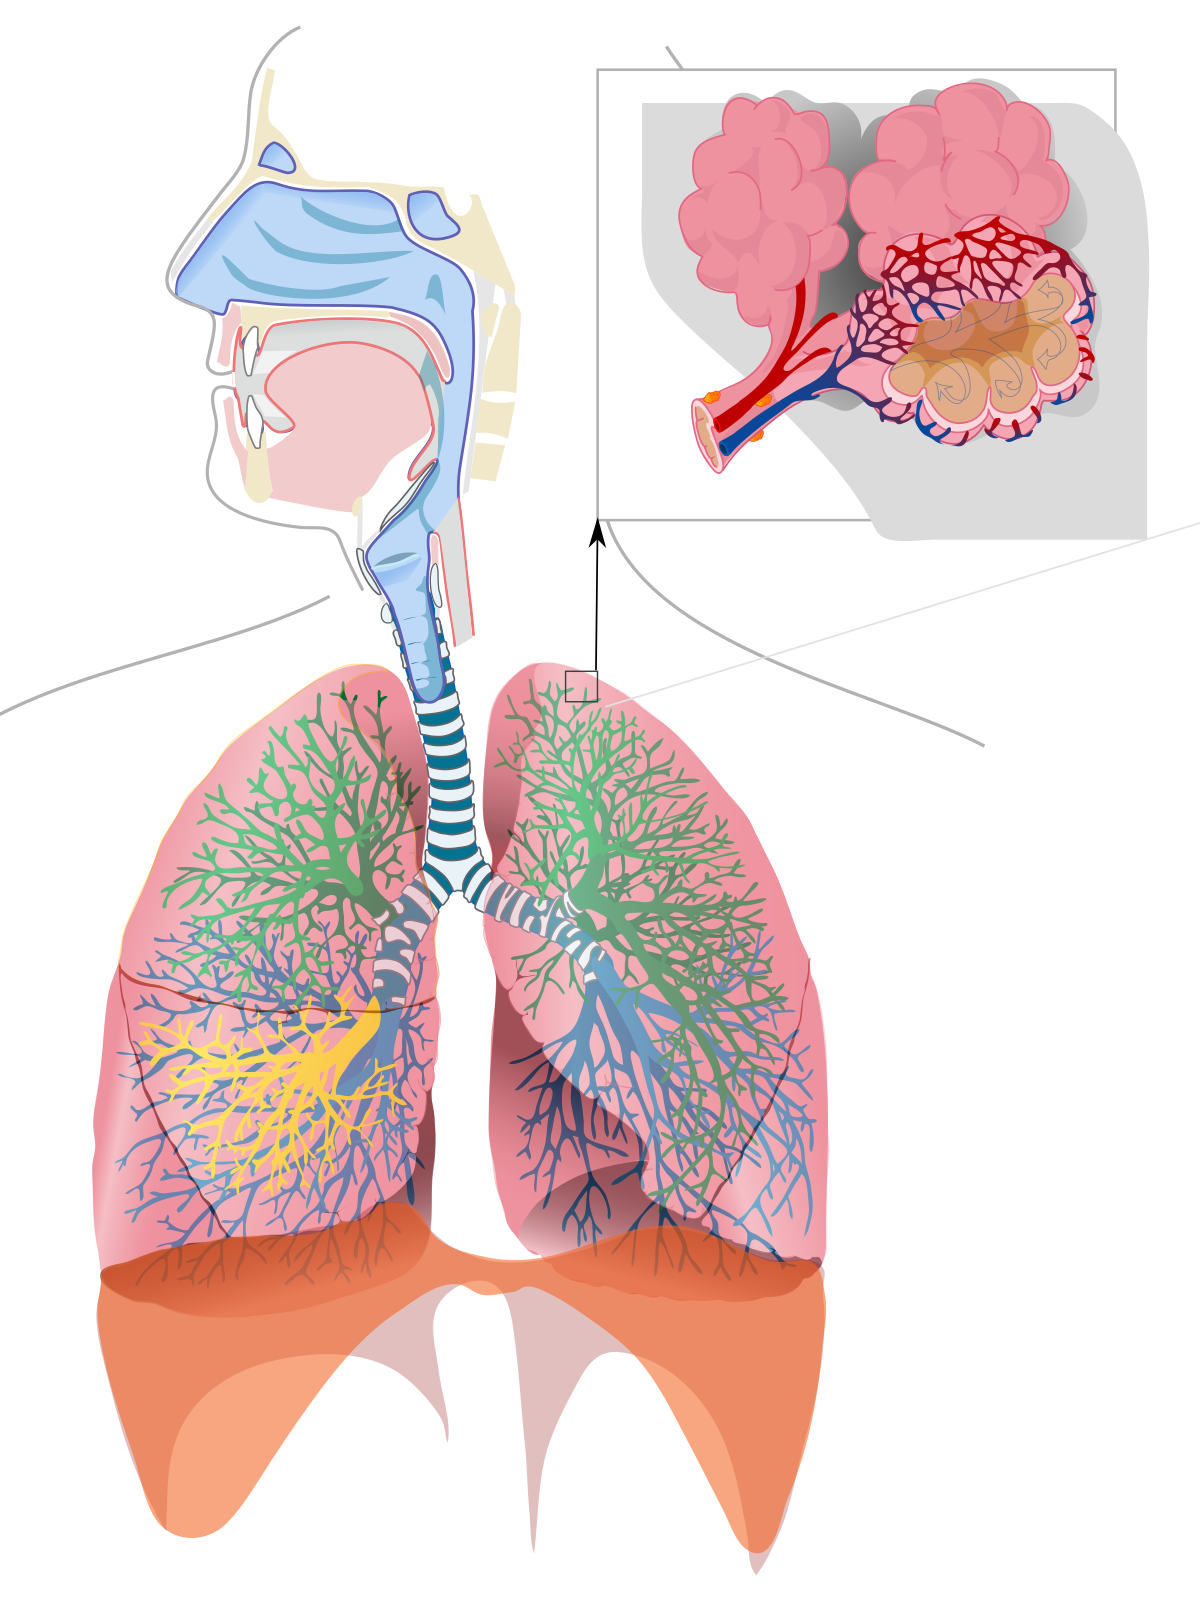

Здоровье дыхательной системы: бронхи и легкие